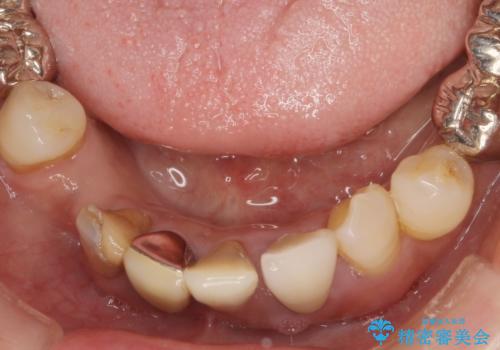

歯周病 全顎治療

- 前歯の見た目、入れ歯による噛めないことの改善を求めて来院されました。

検査により全顎的な歯周病治療、欠損のインプラント補綴、根管治療が必要な状態であることをお伝えし、治療を計画します。